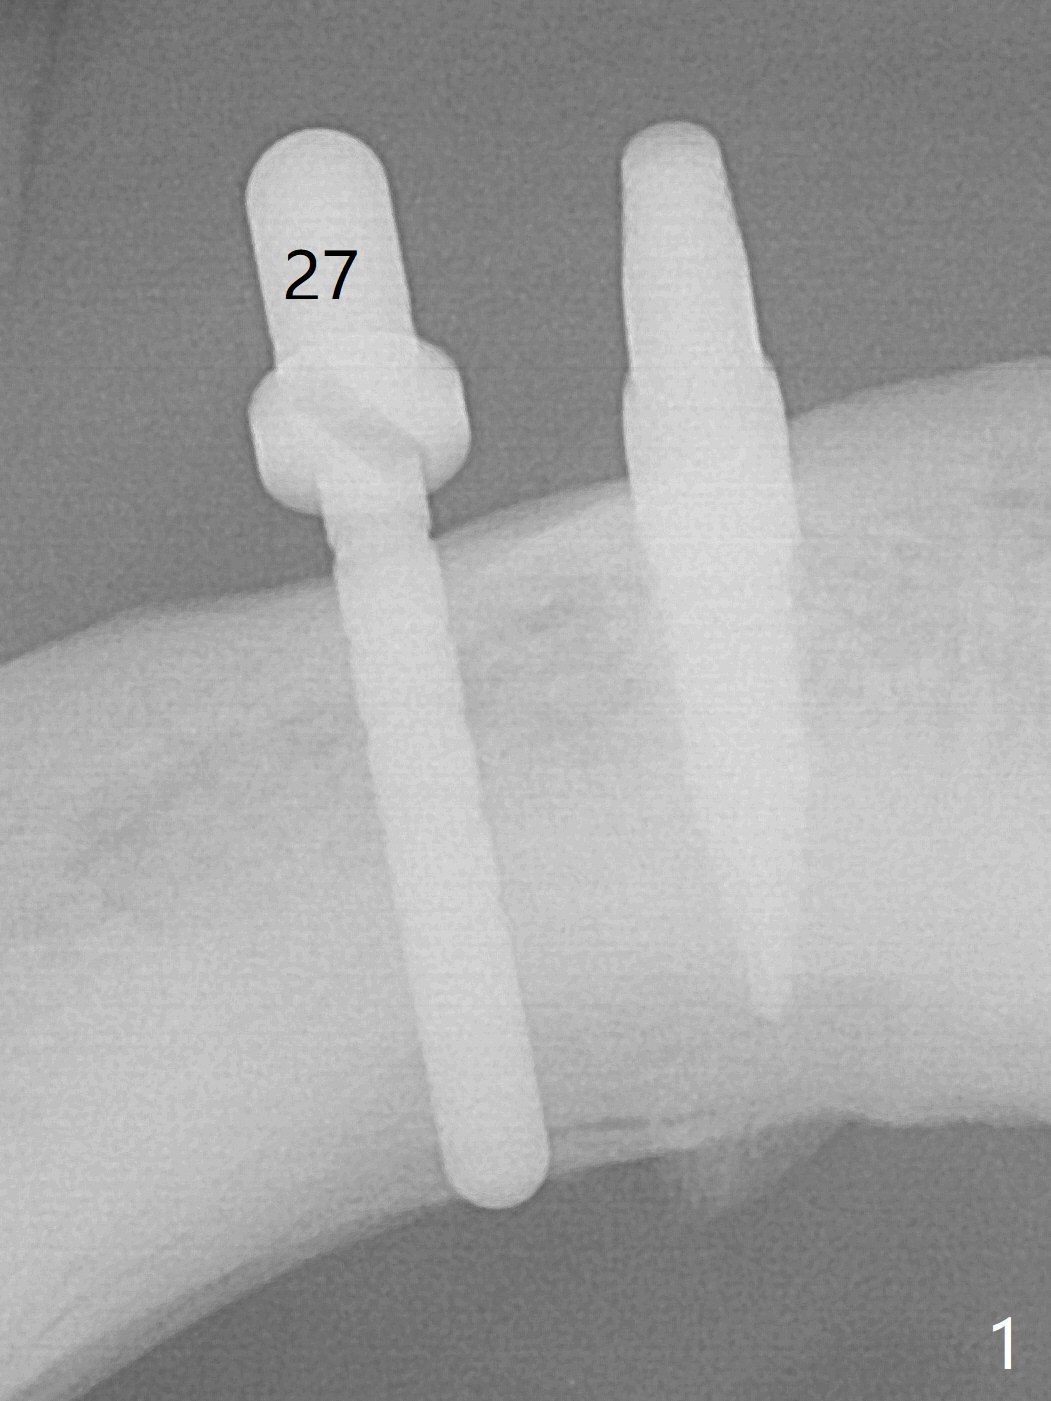

Two months post removal of a loose implant at #27 for the 2nd time, an incision is made. The osteotomy has healed. Initial osteotomy with 2 mm drill for 12 mm leads to sudden empty feeling in spite of lingual plate protection (Fig.1). When the parallel pin is removed, a long explorer does not find the perforation. Subsequent osteotomy depth is 8.5 mm. A 3.8x8.5 mm implant is placed with >40 Ncm (Fig.2). After 5 more turns of the implant, a healing screw is placed (Fig.3,4 *). The wound is closed for infection control. It appears that the previous failures are due to lack of depth control and micromovement (immediate loading). The implant appears to have been osteointegrated 5 months 20 days postop (Fig.5).